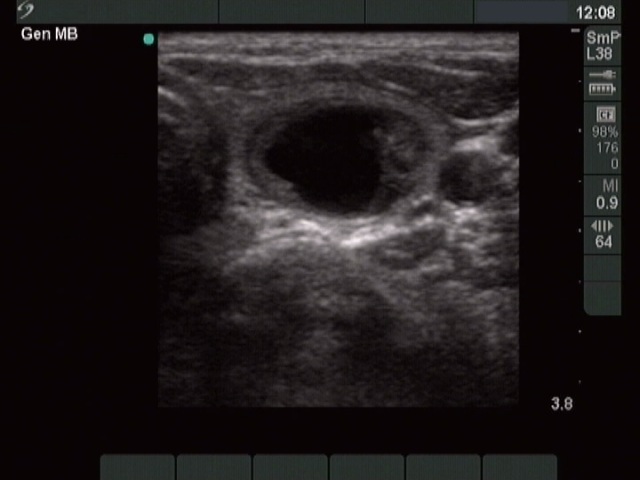

Left lobe, horizontal scan. There is a central-type cystic nodule showing a minimally hypoecogenic solid part.